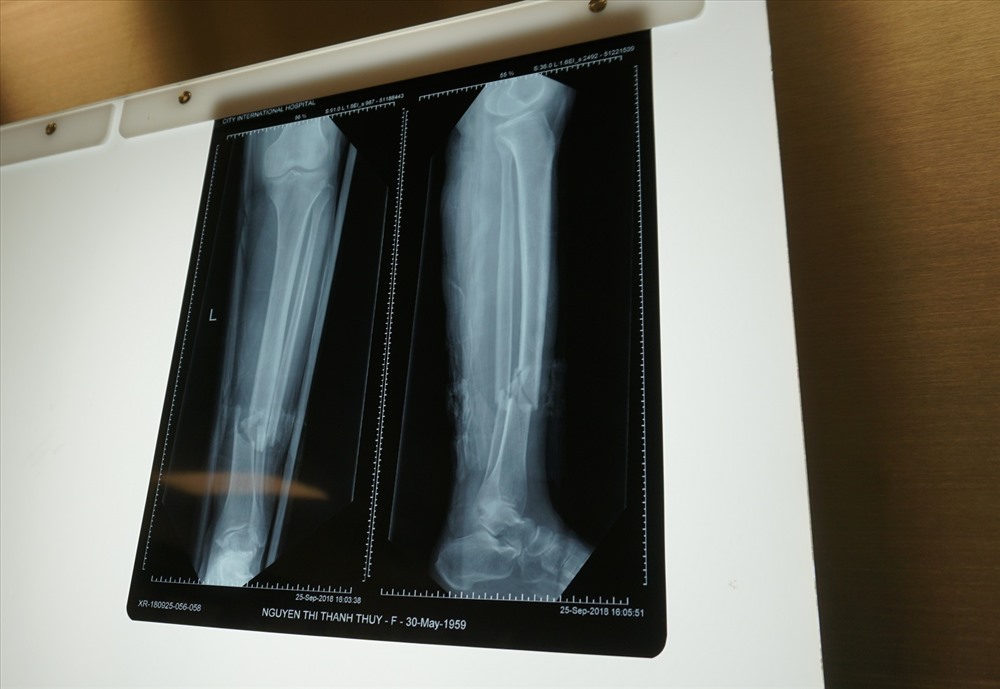

Bệnh nhân bị gãy hở 1/3 dưới hai xương cẳng chân. Ảnh: Báo Lao Động.

Theo VnExpress đưa tin, ngày 25/9, bà T. được bác sĩ chẩn đoán gãy hở 1/3 dưới hai xương cẳng chân trái, xương chày gãy chéo, xương mác gãy ngang, các cơ, mô dập nát nhiều cần phải phẫu thuật ngay. Tuy nhiên, gia đình theo giáo phái “không cho truyền máu người khác” kể cả máu thân nhân nên một số bệnh viện từ chối phẫu thuật.